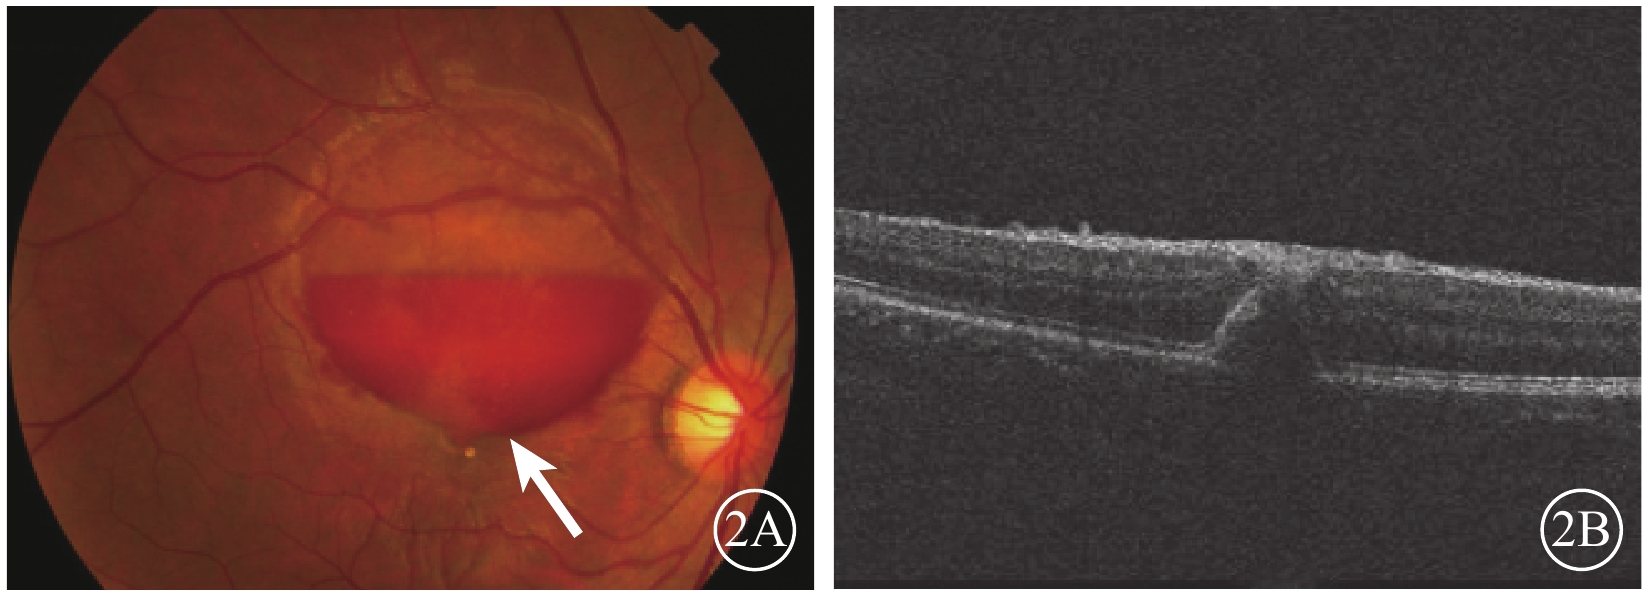

2015年12月7日行摻釹釔鋁石榴石(Nd:YAG)激光積血區內界膜(ILM)切開,最大能量3.5 mJ,單脈沖爆破模式,未見新鮮血液流出。未進行治療觀察。2016年1月27日復查,下方積血吸收邊緣至黃斑區(圖2A)。OCT檢查,黃斑區前ILM增厚,牽拉黃斑中心凹,黃斑正常結構消失(圖2B)。2月23日復查,右眼矯正視力0.25。黃斑區視網膜前出血基本吸收。OCT檢查,黃斑區ILM增厚,可見黃斑板層裂孔(圖3A)。4月20日復查OCT,黃斑中心凹處ILM增厚,中心凹鼻側ILM與其下視網膜組織分離,可見黃斑板層裂孔。仍未治療繼續觀察。8月17日復查,患者訴視物有水波紋樣浮動。OCT檢查,病變處ILM與其下視網膜組織分離,黃斑板層裂孔,黃斑中心凹處ILM較前略增厚(圖3B)。FFA檢查,黃斑拱環縮小,視網膜毛細血管變形稍紆曲,未見熒光素滲漏,可見線狀遮蔽熒光。

圖2

右眼彩色眼底、OCT像。2A. 彩色眼底像,積血較前吸收,下方邊緣至黃斑區(白箭);2B. OCT像,黃斑區ILM增厚,牽拉黃斑中心凹

圖2

右眼彩色眼底、OCT像。2A. 彩色眼底像,積血較前吸收,下方邊緣至黃斑區(白箭);2B. OCT像,黃斑區ILM增厚,牽拉黃斑中心凹

2015年12月7日行摻釹釔鋁石榴石(Nd:YAG)激光積血區內界膜(ILM)切開,最大能量3.5 mJ,單脈沖爆破模式,未見新鮮血液流出。未進行治療觀察。2016年1月27日復查,下方積血吸收邊緣至黃斑區(圖2A)。OCT檢查,黃斑區前ILM增厚,牽拉黃斑中心凹,黃斑正常結構消失(圖2B)。2月23日復查,右眼矯正視力0.25。黃斑區視網膜前出血基本吸收。OCT檢查,黃斑區ILM增厚,可見黃斑板層裂孔(圖3A)。4月20日復查OCT,黃斑中心凹處ILM增厚,中心凹鼻側ILM與其下視網膜組織分離,可見黃斑板層裂孔。仍未治療繼續觀察。8月17日復查,患者訴視物有水波紋樣浮動。OCT檢查,病變處ILM與其下視網膜組織分離,黃斑板層裂孔,黃斑中心凹處ILM較前略增厚(圖3B)。FFA檢查,黃斑拱環縮小,視網膜毛細血管變形稍紆曲,未見熒光素滲漏,可見線狀遮蔽熒光。

圖2

右眼彩色眼底、OCT像。2A. 彩色眼底像,積血較前吸收,下方邊緣至黃斑區(白箭);2B. OCT像,黃斑區ILM增厚,牽拉黃斑中心凹

圖2

右眼彩色眼底、OCT像。2A. 彩色眼底像,積血較前吸收,下方邊緣至黃斑區(白箭);2B. OCT像,黃斑區ILM增厚,牽拉黃斑中心凹